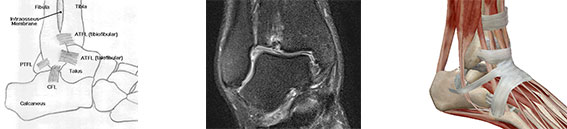

- Anatomia prawidłowa stopy, stawu skokowego i ścięgna Achillesa.

- Anatomia „obrazowa” stopy, stawu skokowego i ścięgna Achillesa.

- Metody obrazowania struktur stopy, stawu skokowego i ścięgna Achillesa – RTG, USG, artrografia, TK, MR, artro-TK i artro-MR.

- Magia skrótów: ATFL, PTFL, CFL, AITFL, PITFL, TTFL, IOL, TNL, TCL, TTL, DATTL, DPTTL… różne uszkodzenia …